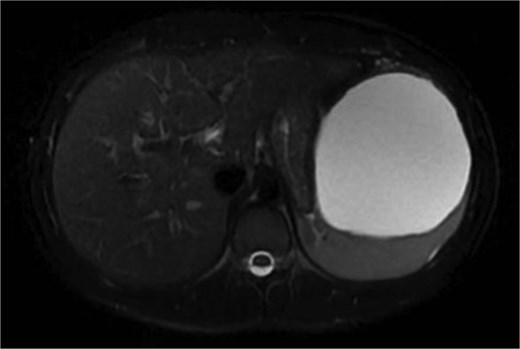

We present a 22-year-old female patient with no relevant past medical history who, 6 months prior to diagnosis, began experiencing mild abdominal pain and distension in the upper abdomen. Laboratory studies showed a white blood cell count of 9500/μl, lymphocytosis of 19%, and neutrophilia of 74.1%. Magnetic resonance imaging reported a giant splenic cyst, ~13 cm (Figs 1 and 2).

Axial view or preoperative MRI of splenic cyst, diameter of 13 cm.